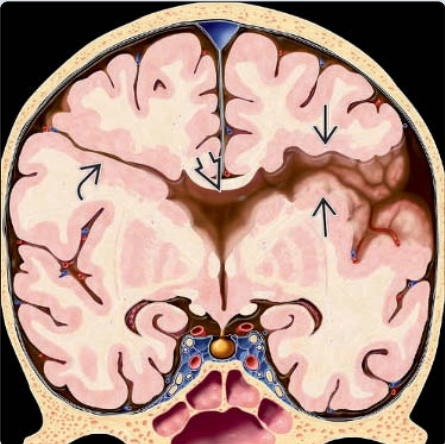

Não trước không phân chia thể không phân chia (Alobar holoprosencephaly)